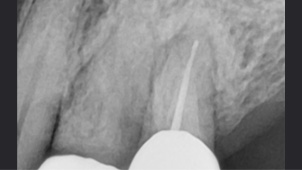

치주 치료로 재생된 건강한 잇몸

잇몸건강이 회복된 앞니는 크라운으로 수복